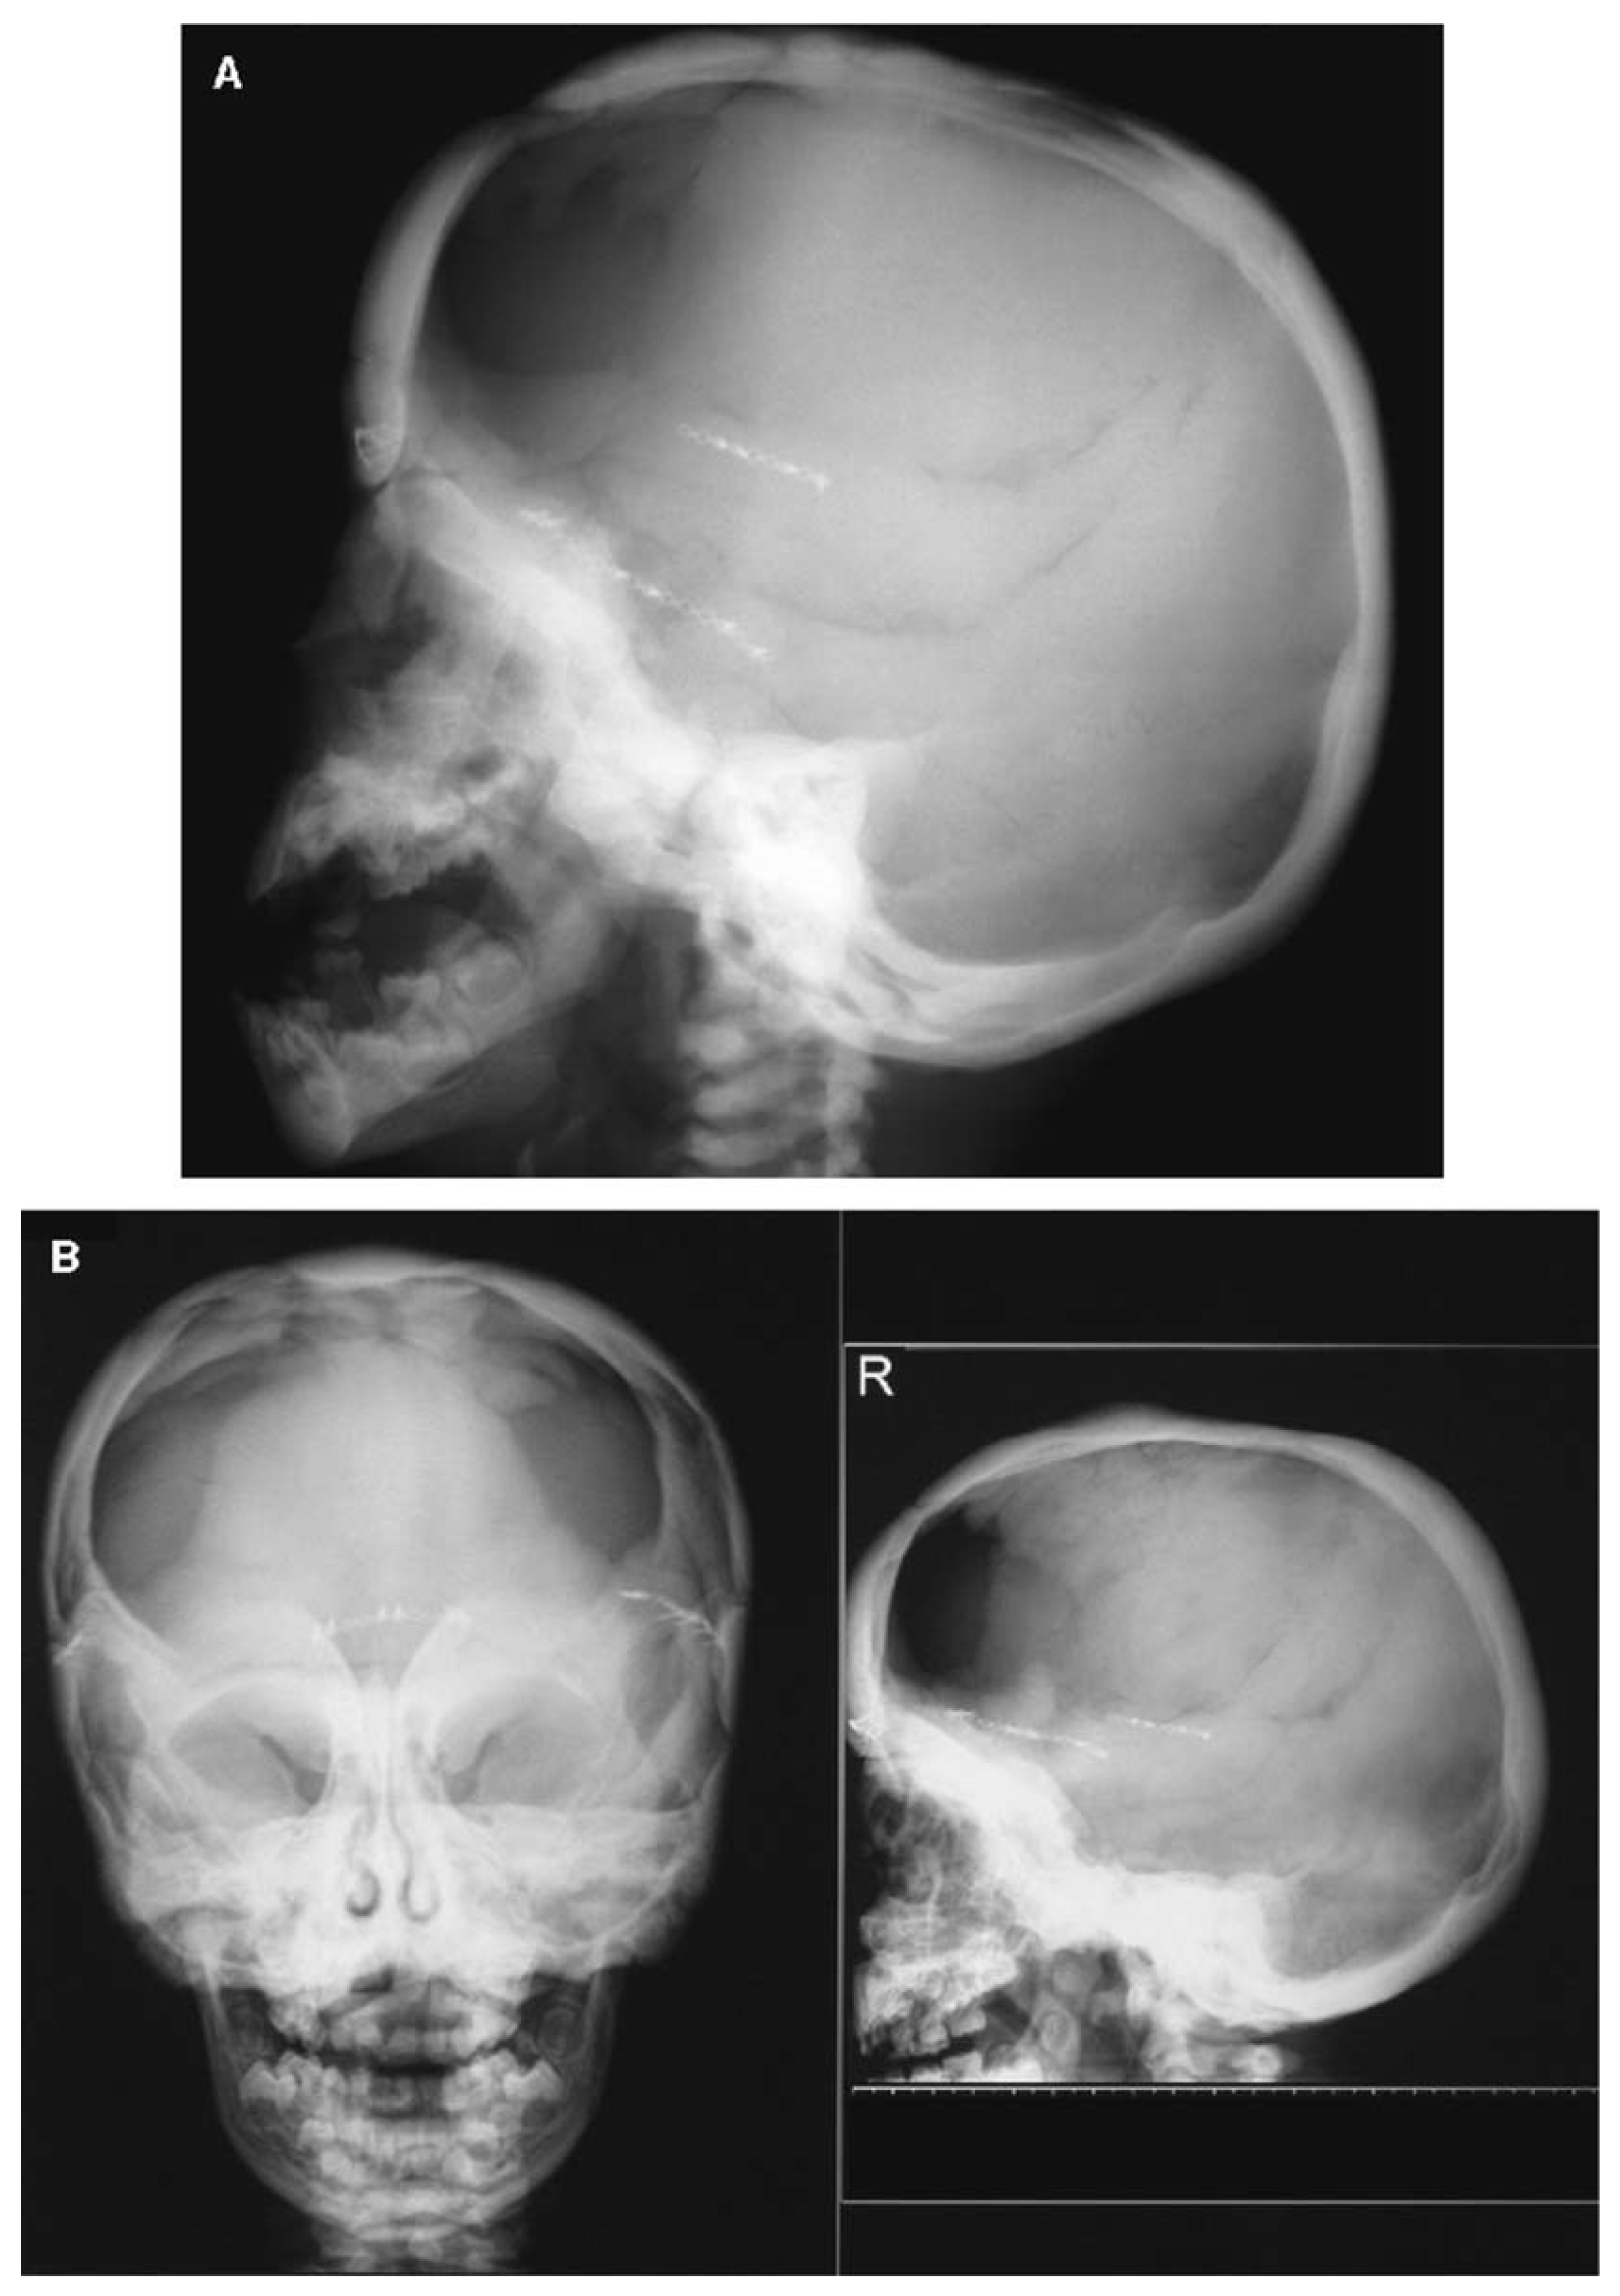

- Littman, J.; Phornphutkul, C.; Saade, C.; Katarincic, J.; Aaron, R. Osteoporosis, Fractures, and Blindness Due to a Missense Mutation in the LRP5 Receptor. Orthop. Res. Rev. 2023, 15, 39–45. [Google Scholar] [CrossRef] [PubMed]